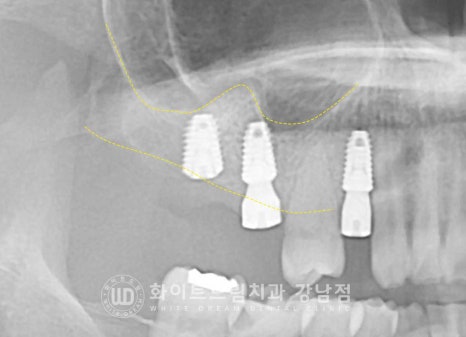

이 중에서 상악 16,17번 치아 부위는

치아를 발치한지 오랜 시간이 지나 잇몸뼈의 함몰과 상악동의 함기화가

일어나 임플란트를 식립하기에는 잇몸뼈의 양이 많이 모자란 상태였습니다.

이럴 때 상악동을 살짝 들어 올린 후 모자란 뼈를 형성하는 방법이

바로 '상악동 거상술'이랍니다.

상악동의 얇은 막을 들어 올려, 그 빈 공간에 뼈이식재를 넣어 새로운 뼈를 형성해 주는 방법으로

환자분의 경우 많은 양의 잇몸뼈가 필요했기에

볼 쪽 잇몸뼈에 작은 창문을 내어 진행하는 lateral, 측방 접근법을 동반하게 되었습니다.

▲ 상악동 거상술 & 임플란트 수술 후 (23.03.07)